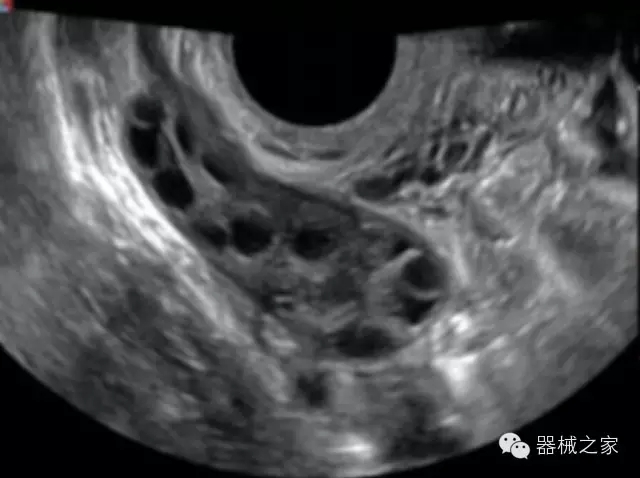

臨床圖片賞析